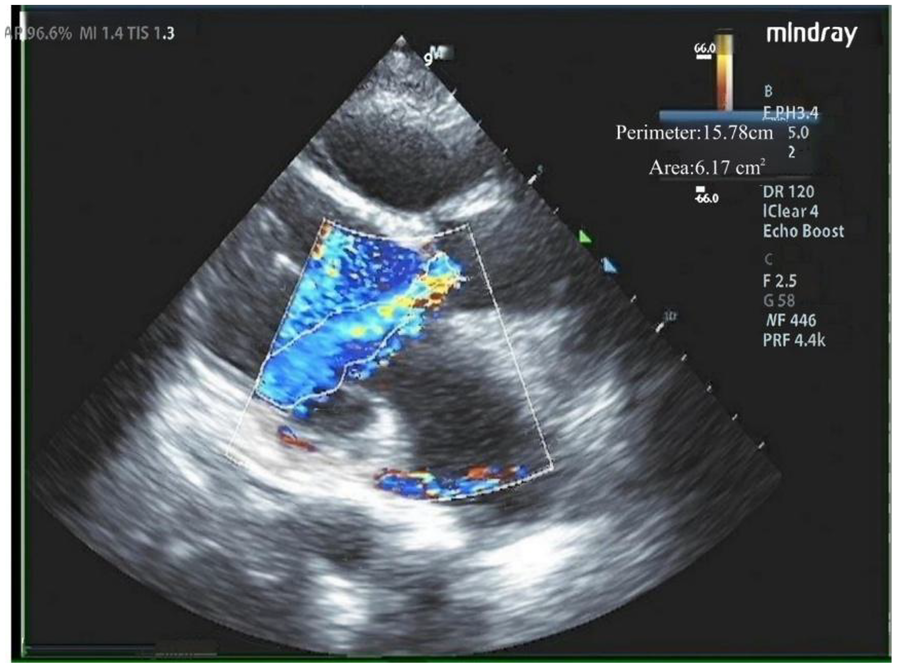

Our hospital admitted a 53-year-old female patient who presented with a chief complaint of “intermittent chest discomfort for 4 years, with exacerbation over the past week”. In 2020, the patient experienced chest discomfort after physical activity, accompanied by shortness of breath and palpitations. She was subsequently diagnosed with ischemic cardiomyopathy and heart failure at a local hospital. Despite receiving guideline-directed medical therapy (GDMT), her condition persisted with recurrent symptoms and progressive worsening. Consequently, on May 8, 2021, she was initiated on continuous renal replacement therapy, utilizing continuous venous-venous hemofiltration. On May 25, 2022, the patient underwent implantation of a LVAD (HeartCon model) in conjunction with coronary artery bypass grafting (CABG). Postoperatively, her symptoms improved significantly, allowing for discharge. However, in June 2024, the patient presented again with chest discomfort and was admitted to our hospital for further evaluation. At admission, the parameters of LVAD were as follows: pump speed 2,300 rpm, power 5.10 W, and flow rate 7.85 L/min. Laboratory tests revealed an elevated N-terminal pro-B-type natriuretic peptide (NT-proBNP) level of 4,864 pg/ml. Echocardiography indicated moderate to severe regurgitation of the aortic valve (Figure 1).

Figure 1

Moderate to severe regurgitation of the aortic valve.